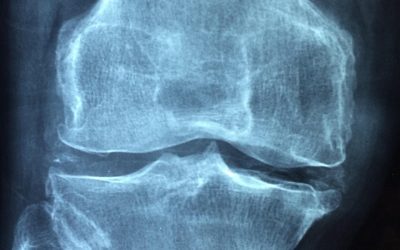

Rehabilitación de Rodilla: guía integral basada en la ciencia

La rehabilitación de rodilla es un proceso esencial para recuperar la movilidad y funcionalidad tras lesiones o intervenciones quirúrgicas, siendo cada vez más importante tanto en entornos clínicos como a la hora de realizar una rehabilitación de rodilla en casa. Con...

Recuperación de una Operación de Menisco: Readaptación Deportiva en base a la ciencia

La recuperación de una operación de menisco es un proceso vital para quienes desean volver a su deporte al máximo nivel tras una cirugía. La readaptación deportiva va más allá de la fisioterapia convencional, abarcando estrategias específicas y personalizadas que...